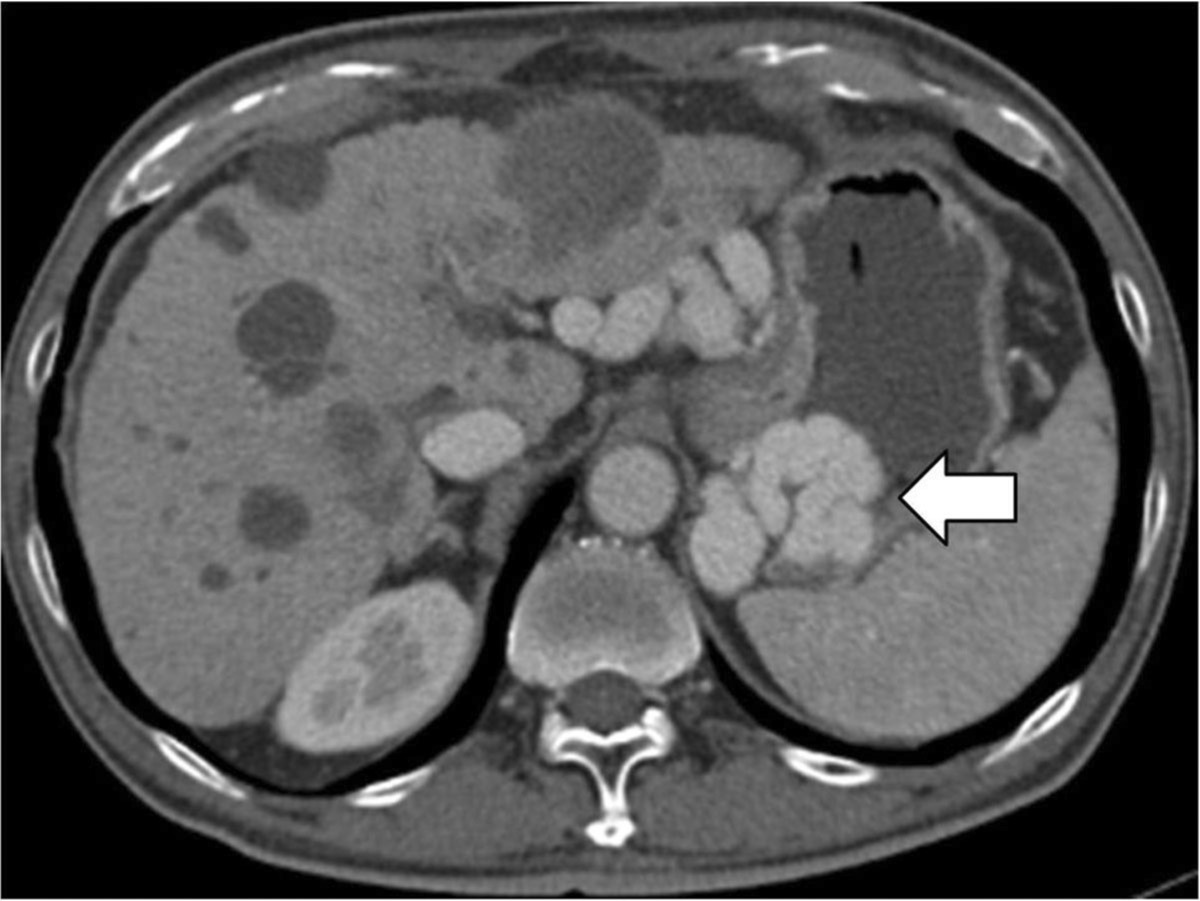

조영증강 복부전산화단층촬영에서 위기저부의 정맥류가 보이지만, 간내부의 문맥은 보이지 않고, 주문맥도 막혀 있음(Fig 1).

Fig. 1. Contrast enhanced CT scan of the abdomen demonstrates that the gastric fundal varies(arrow), nonvisulization of the intrahepatic portal vein and main portal vein occlusion.